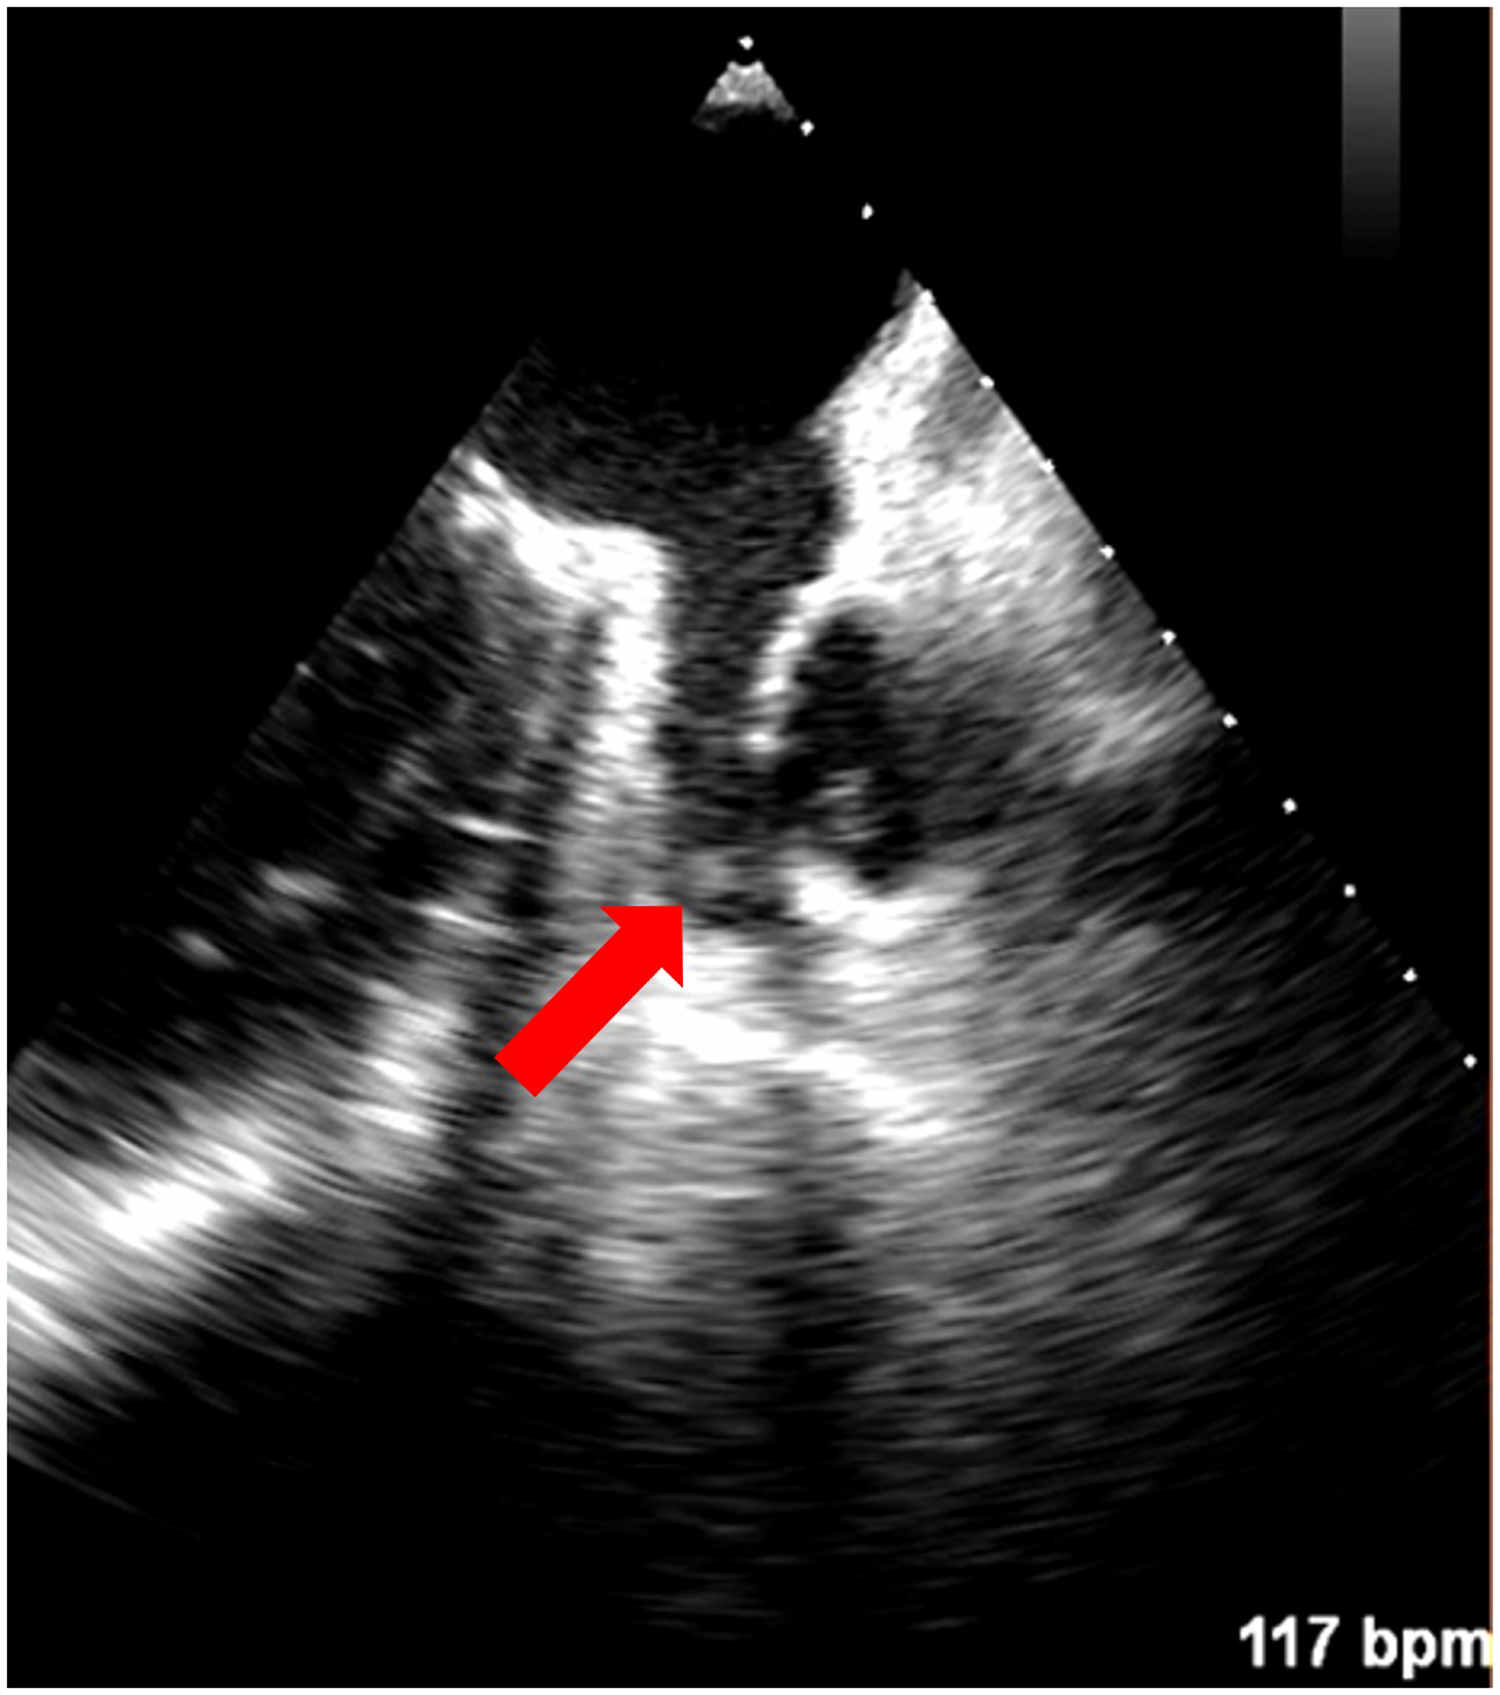

In 67 patients (94.4%), both TEE and CMR excluded the presence of LAA thrombus. In 1 patient (1.4%), both TEE and CMR showed the presence of thrombus [Figures 1, 2; a supplementary movie file shows the thrombus detected with TEE in motion (see Supplementary Video S1)].

Figure 2

Left atrial appendage thrombus indicated with a red arrow on TEE (Heart and Vascular Center, Semmelweis University).